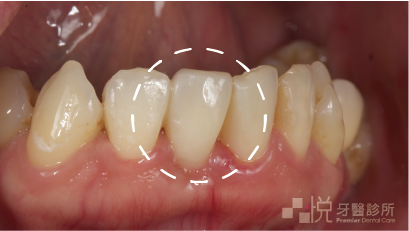

臨時馬利蘭牙橋中看但是不中用,所以我千叮嚀萬交代回去絕!對!不!可!以!用門牙啃東西吃,食物要放到側邊的牙齒咀嚼。阿婷可能這次也嚇到了,所以非常遵守我的醫囑,於是這組臨時牙橋相安無事的度過了拔牙傷口的恢復期。

傷口恢復的期間,我們也針對了牙齒狀況重新做了一次討論。因為他未來有要做矯正的打算,所以在這個時候植牙重建不會是一個適合的方式。再考量到兩側的牙齒結構大致上還算完整,我向他建議了馬利蘭牙橋這種相對很保守的缺牙重建方式。

接下來,我開始調整臨時馬利蘭牙橋的型態,結此來引導缺牙區域的牙齦外型恢復得更自然。等到牙齦及牙齒的外型功能健康性都穩定後,就是正式馬利蘭牙橋製作的部分啦。